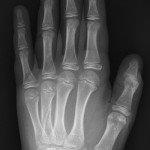

Metacarpal fractures (2nd to 5th)

Undisplaced extra-articular fractures with NO rotational deformity

- Resting volar slab and follow up with Plastic Surgery clinic in 1-2 days.

Displaced, angulated, intra-articular fractures or rotational deformity

- Most common is 5th "Boxer's Fracture".

- Reduce fracture under nerve block +/- sedation if appropriate. Otherwise refer to Plastic Surgery team.